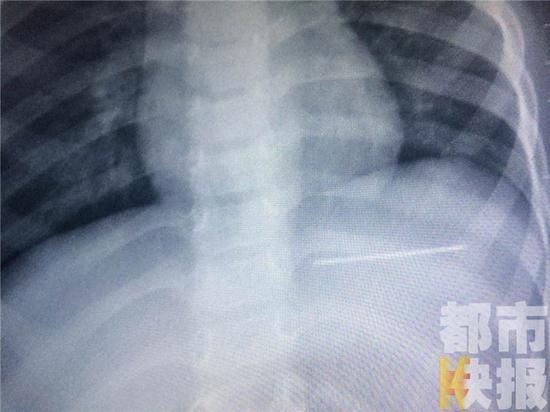

钢针,缝个被子补个衣服,家家户户都在用。可图中这根生了锈的钢针,却让人心痛,因为,它是刚从一个两岁多男童的肚子里取出来的。

经过再次确认,原来孩子的肚子有一根接近5公分的钢针,而且位置比较危险。

医生:“膈肌的上头就是心脏,它刚好扎在膈肌下头,而且从视频上可以看到心脏还在上边跳。”确认完毕后,医生立即展开手术。

手术进行了一个多小时,最终,这根扎在孩子肚子里的钢针终于被取了出来。